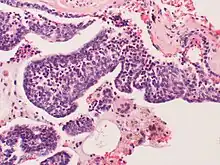

Pulmonary neuroendocrine cells (PNECs) are specialized airway epithelial cells that occur as solitary cells or as clusters called neuroepithelial bodies (NEBs) in the lung. Pulmonary neuroendocrine cells are also known as bronchial Kulchitsky cells.[2] They are located in the respiratory epithelium of the upper and lower respiratory tract. PNECs and NEBs exist from fetal and neonatal stages in the lung airways.

These cells are bottle- or flask-like in shape, and reach from the basement membrane to the lumen. They can be distinguished by their profile of bioactive amines and peptides, namely serotonin, calcitonin, calcitonin gene-related peptide (CGRP), chromogranin A, gastrin-releasing peptide (GRP), and cholecystokinin.

These cells can be the source of several types of lung cancer, most notably small cell carcinoma of the lung, and bronchial carcinoid tumor.[3][4]